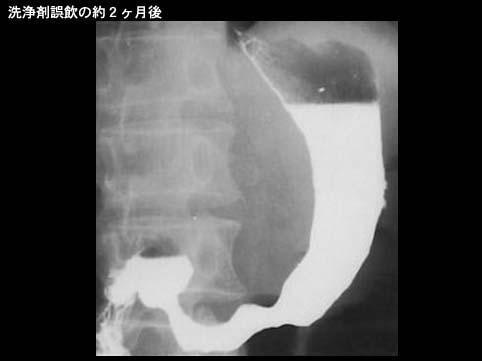

질환(병리주체)의 분류 염증성 및 궤양성질환/부식성 위염

검사방법 X-P